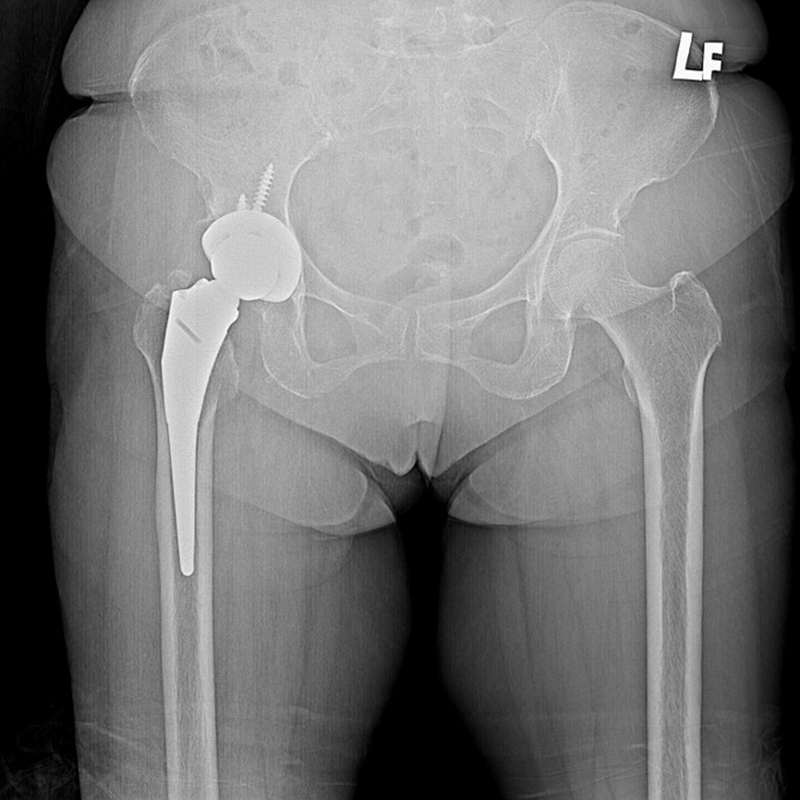

傳統髖關節置換 首頁 案例分享 髖關節手術 傳統髖關節置換 54歲蔡先生退化性關節炎 術前 術後 張女士 51歲 退化性關節炎(DDH先天發育不全 CROWE TYPE 2) 術前 術後 38歲林先生 退化性關節炎 術前 術後 72歲謝女士 退化性關節炎 術前 術後 71歲 謬女士 骨股頭壞死 術前 術後 50歲 郭先生骨股頭壞死 術前 術後 80歲 盧先生骨股頭壞死 術前 術後 林先生 37歲 術前 術後 邱女士 51歲 術前 術後 張女士 50歲 術前 術後